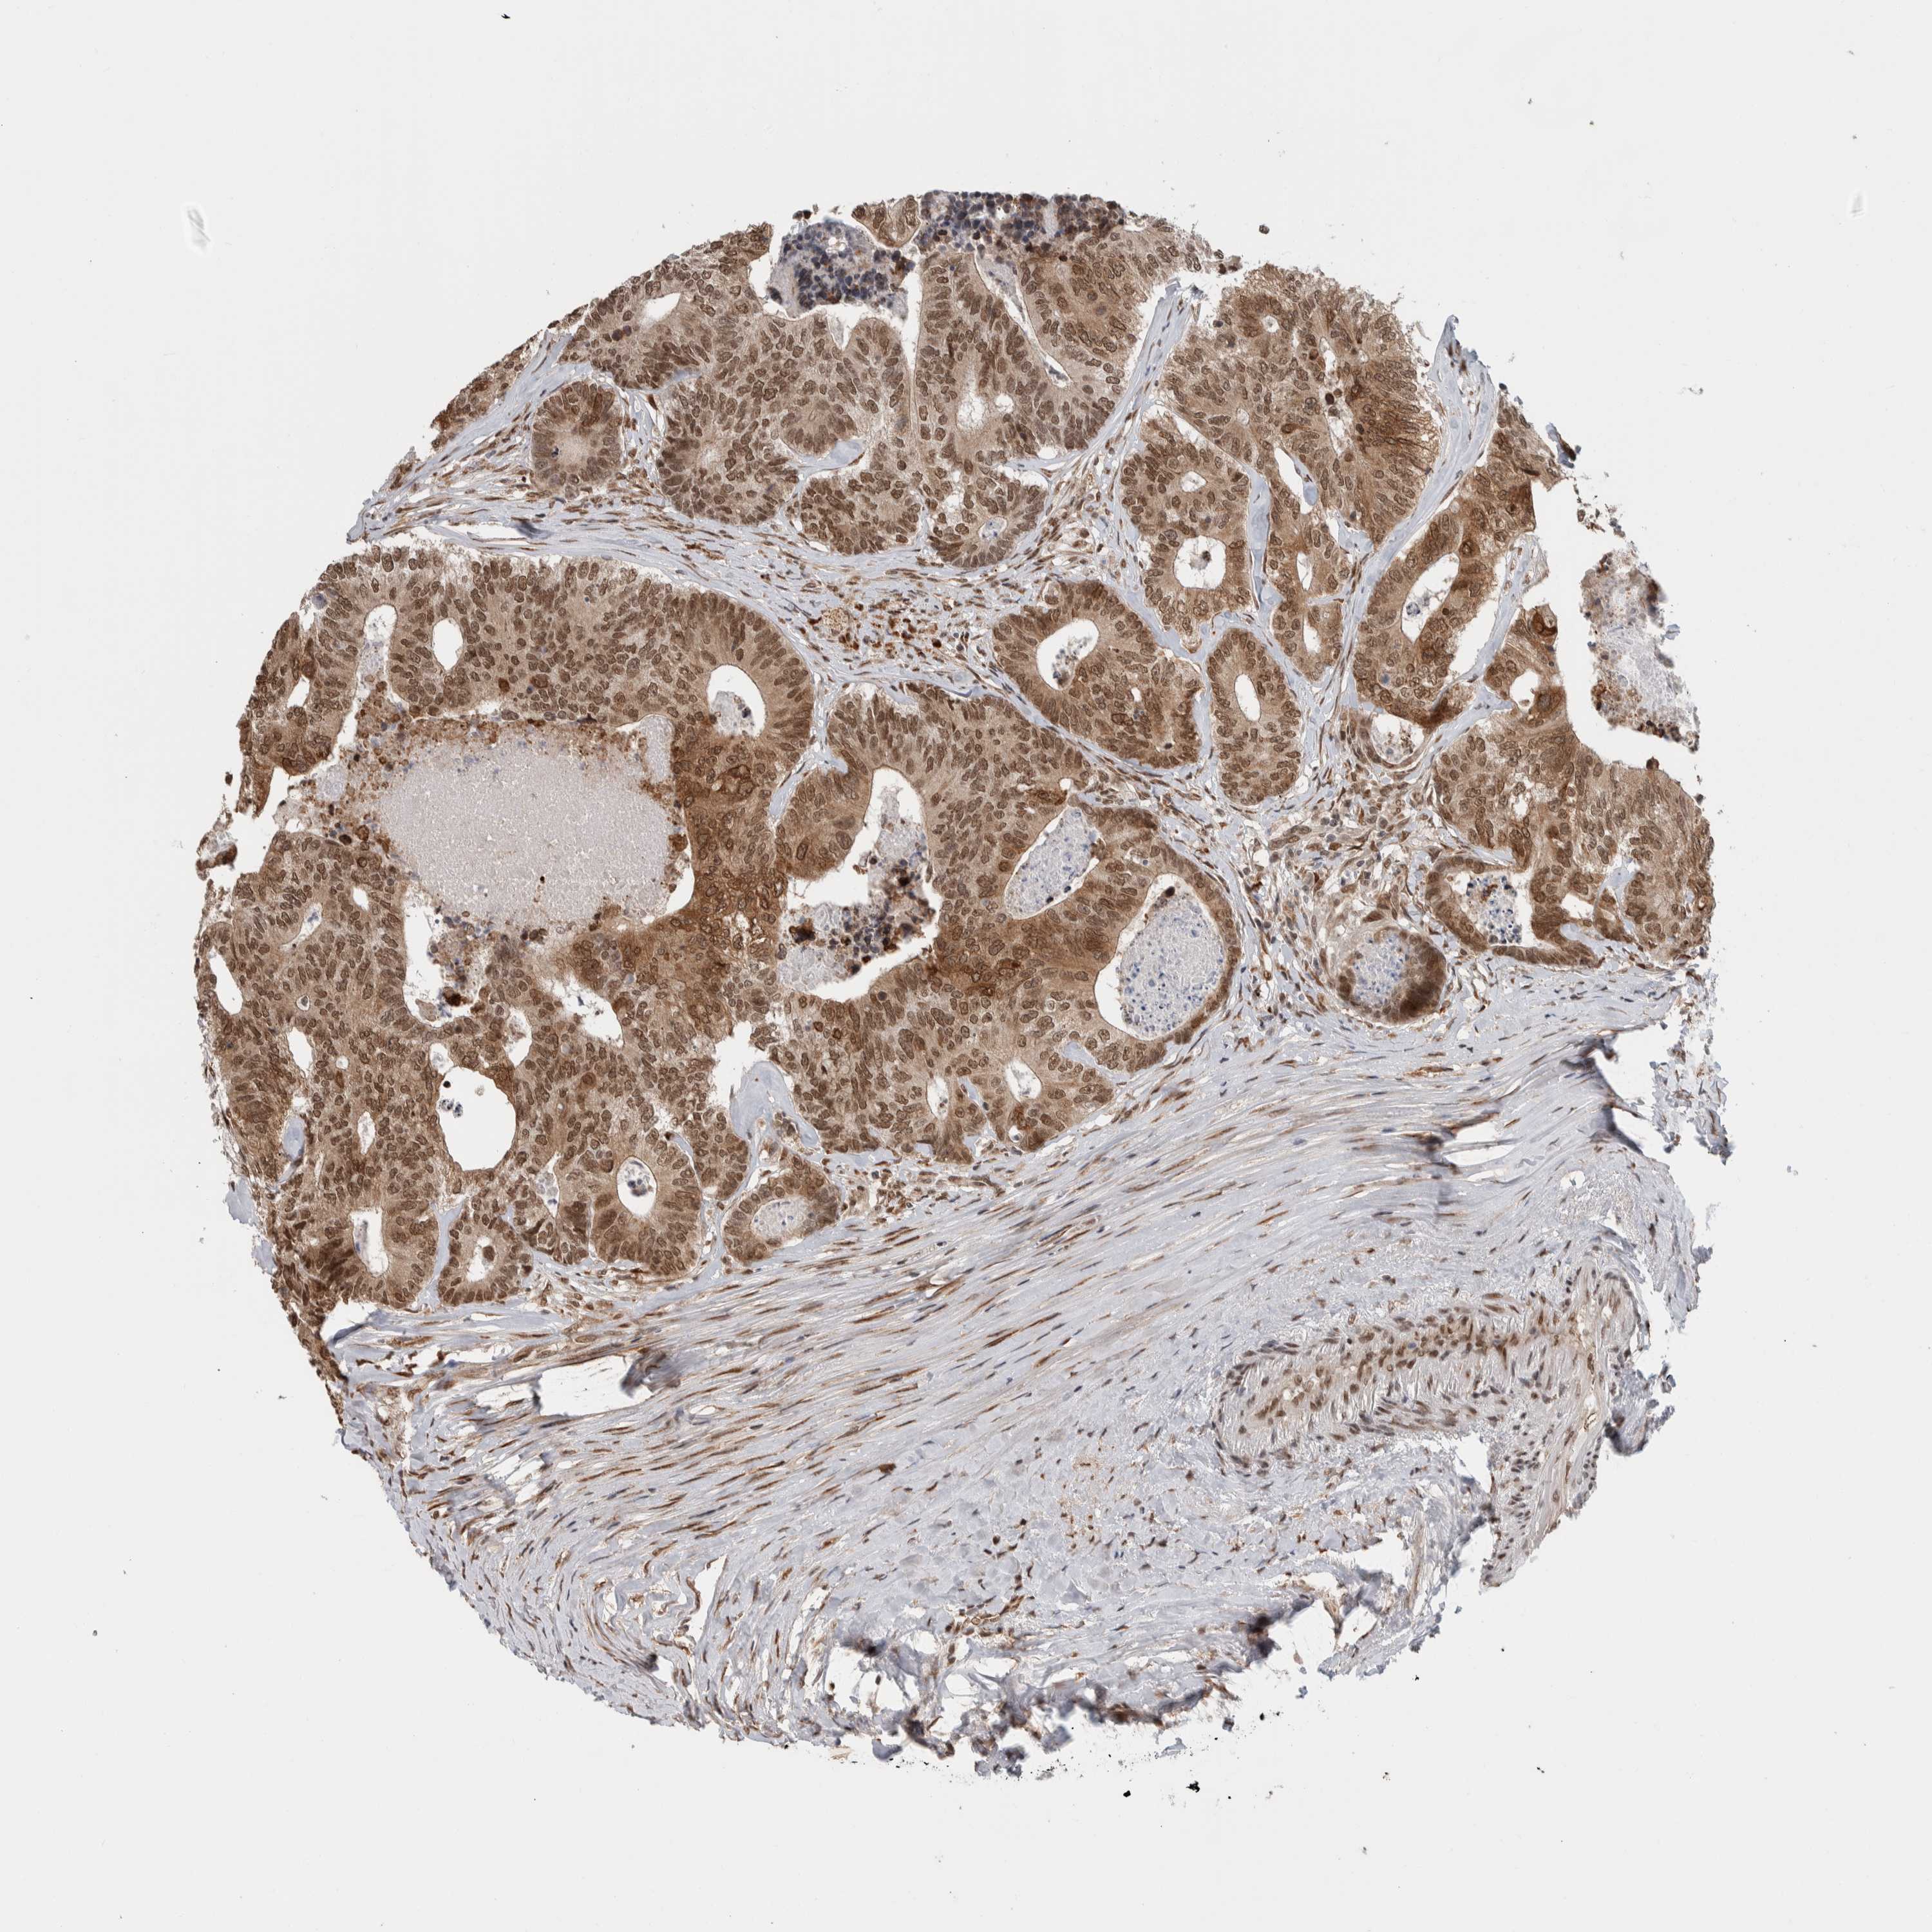

CANCER COLORECTAL CANCER Show tissue menu

Colorectal cancer

Human cancer

Colon adenocarcinoma

Rectum adenocarcinoma